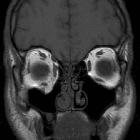

CT

CT is the modality of choice for assessment of the facial skeleton. A full assessment does not require the administration of contrast. Ideally, the acquisition should be performed using the thinnest detector settings, enabling thin-slice reconstructions along three orthogonal planes with a bone algorithm. Additional soft tissue algorithm reconstructions using larger slice thickness and 3D volumetric reconstruction are useful for assessing associated soft tissue injury and gauging facial asymmetry, respectively.

In addition to evaluating the location and extent of fracture(s), other features requiring assessment and reported include:

- presence of intraorbital (usually extraconal) hemorrhage: may result in stretching or compression of the optic nerve

- globe injury/rupture

- extraocular muscle entrapment: suspected if there is an acute change in angle of the muscle

- prolapse of orbital fat